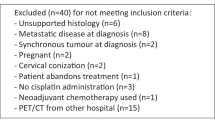

In this retrospective cohort study, we enrolled 170 patients (median age, 55 years) newly diagnosed as having cervical cancer at China Medical University Hospital between July 2009 and December 2015. All the patients had undergone pretreatment (18F-FDG PET/CT) for radiotherapy planning or pretreatment staging. Patients with a history of diabetes were excluded, and all the patients had normal serum glucose levels before undergoing PET/CT. The minimum size of the eligible criteria for the primary tumors was maximal diameter ≧2 cm in computed tomogram. Only primary tumors were considered because a reliable textural analysis of small lesions is difficult owing to the small number of voxels involved. This study was approved by a local institutional review board [DMR99-IRB-010(CR6)]. We performed tumor staging according to the International Federation of Gynecology and Obstetrics (FIGO) and observed that 41, 91, 35, and 3 patients had stage I, II, III, and IVA cancers, respectively. PET/CT has a high sensitivity and specificity for detecting the nodal status in cervical cancer [15–17]; therefore, it was performed for diagnosing pelvic LNs (PLNs) or para-aortic LN (PALN) metastasis [16]. Briefly, experienced nuclear medicine physicians performed a visual analysis by using a five-point scoring system (0, normal; 1, probably normal; 2, equivocal; 3, probably abnormal; and 4, definitely abnormal), which had been routinely used in interpreting FDG PET/CT images in our institution. We used dichotomous variables in this study: a score 3 or 4 was considered to have LN metastasis, and score 0, 1, or 2 was regarded as absence of metastasis. Accordingly, we identified ≥1 PLNs and ≥1 PALNs in 84 and 25 patients, respectively. Table 1 lists the patient characteristics.